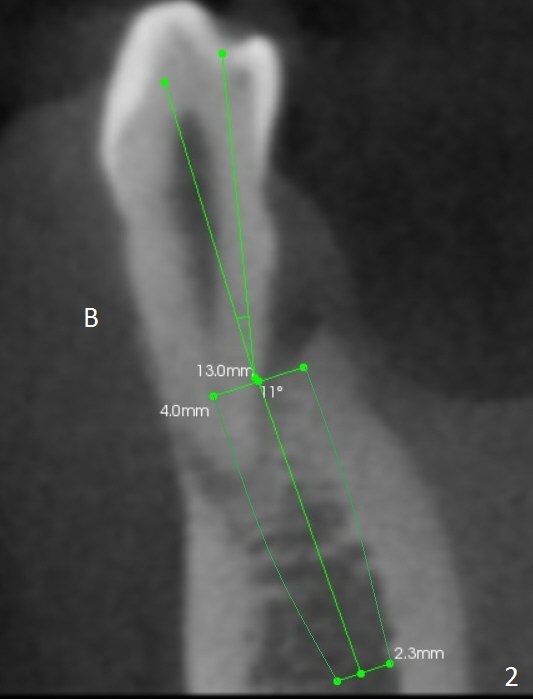

A 44-year-old man will return for #28 extraction and immediate implant 2-3 months after removal of the implant at #31 (Fig.1). After Clindamycin treatment, start osteotomy in the middle of the lingual wall of the socket (Fig.2,3 red line) with 1.6 mm for 13 mm (from oblique to straight). Take PA to determine clearance from the Mental Loop (Fig.1 red dashed line). If the trajectory is right, use 3.3 mm Magic Drill (MD) and possibly 3.8 mm one for short distance, since the bone density near the socket 700 units, while apically 100 units. Or use a 4x11 mm IBS dummy implant instead of 3.8 mm MD. An angled abutment may be used (Fig.2). Also prepare UF in case the gingiva is thick.